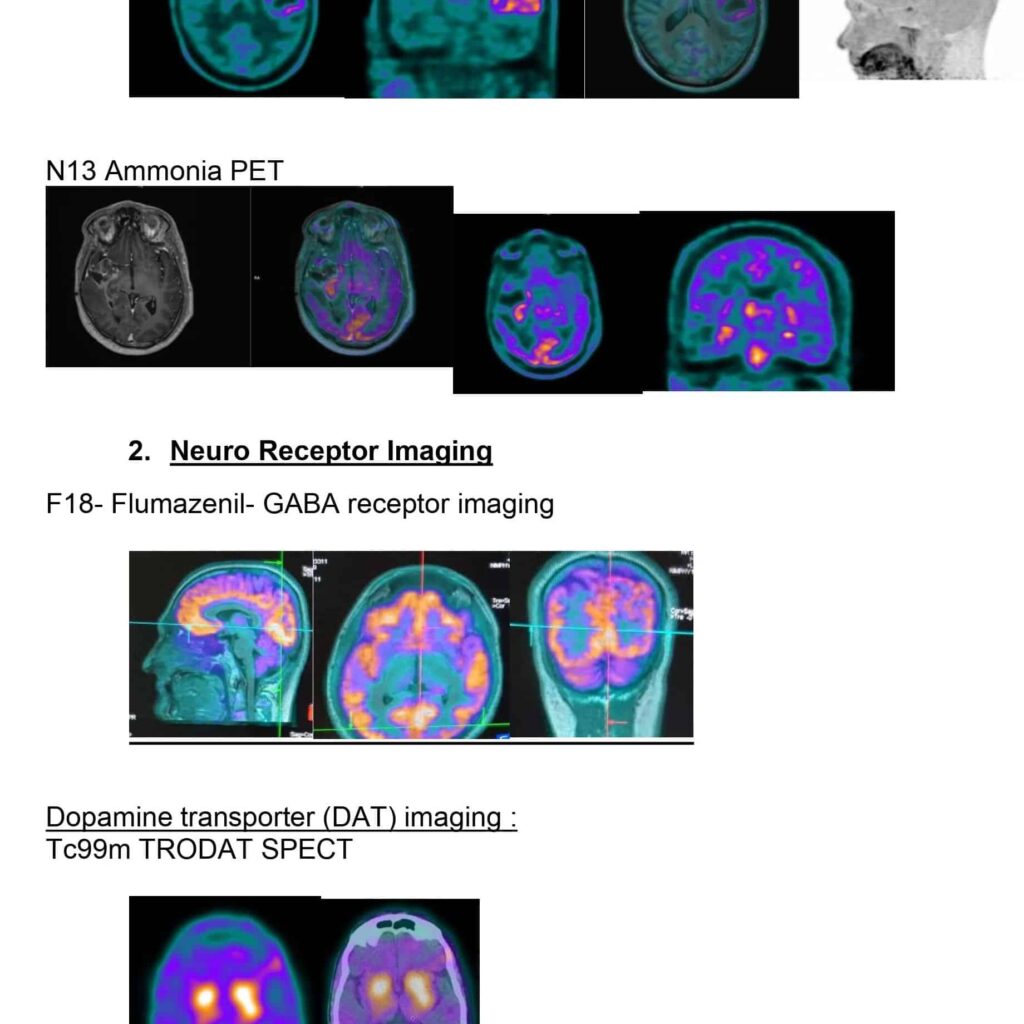

- In 2018, with the licensing of Medical Cyclotron, we became self-reliant and started in-house production of all radiopharmaceuticals for clinical use. Apart from F18 based glucose radiotracers we also started synthesis of amino acid radiopharmaceuticals and neuroreceptor based radiotracers for patient care for the first time in the country.

- Amino acid imaging tagging methionine, choline and tyrosine added more precision to tumor imaging and could change the management strategy in several patients.

- Dopamine imaging using TRODAT or FDOPA has become a crucial diagnostic tool in patients with Parkinson’s disease allowing higher confidence in their diagnosis.

- In the field of research, in vivo imaging of GABA receptors in human brain and with the synthesis of 18F- AVT11 imaging p-glycoprotein expression was initiated with the synthesis of F18 Flumazenil.